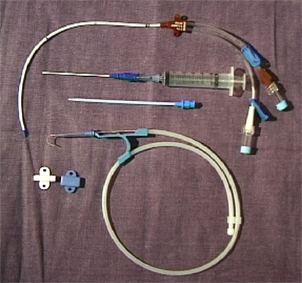

Je nach Art, Osmolarität, Volumen und Kompatibilität der zu applizierenden Substanzen sowie voraussichtlicher Nutzungsdauer gibt es unterschiedliche Kathetersysteme.

-Nicht tunnelierte externe Katheter für peripheren oder zentralen Zugang.

-Tunnelierte Katheter einlumig dünn aus Silikon für TPN, mehrlumig dick aus Silikon für Apherese, Dialyse und Knochenmarkstransplantation.

-Ports für gelegentliche Anwendung über langen Zeitraum (Chemotherapie).

PICC

Goldstandard ist die Punktion der rechten Vena jugularis/anonyma supraklavikulär nach oder unter sonographischer Kontrolle. Die Sonographie muß Lagevarietäten klären und Thrombosen nach früherer Katheterisierung ausschließen.

Die Vena jugularis/ Vena anonyma kann nach Yoffa zwischen medialem und lateralem Kopf des Musculus sternocleidomastoideus von ventral punktiert werden oder horizontal von lateral. Diese Methode wurde 1972 von den amerikanischen Herzchirurgen Garcia, Mispireta und Pinho nach ausführlichen anatomischen Präparationen als einfachster und ungefährlichster Zugang beschrieben. Das Zielgebiet, der Zusammenfluß von Vena jugularis und Vena subclavia zur Vena anonyma ist so groß, dass die Punktion auch ohne Sonographie immer beim ersten Stich gelingt.

Die Punktion von ventral kann unter realtime Sonographie mit einem Standardschallkopf wegen des geringen Abstands zur Clavicula nur in der kurzen Schallachse erfolgen, wobei die Nadel nur abschnittsweise sichtbar ist. Mit dem kleinen 22 MHz Fingerschallkopf aus der Rheumatologie ist auch eine Punktion in der langen Schallachse möglich.

Tunnelierung und Port

Langzeitkatheter und Portkatheter werden von der Punktionsstelle supraklavikulär 4 - 6 cm bis zum Thorax tunneliert.

Da tunnelierte Katheter eine fixe Länge haben, muß die Austrittsstelle exakt vermessen werden, dass einerseits die Katheterspitze im Vorhof bzw. der Vena cava superior liegt, andererseits der Tefloncuff mindestens 2 cm von der Austrittsstelle entfernt im Tunnel.